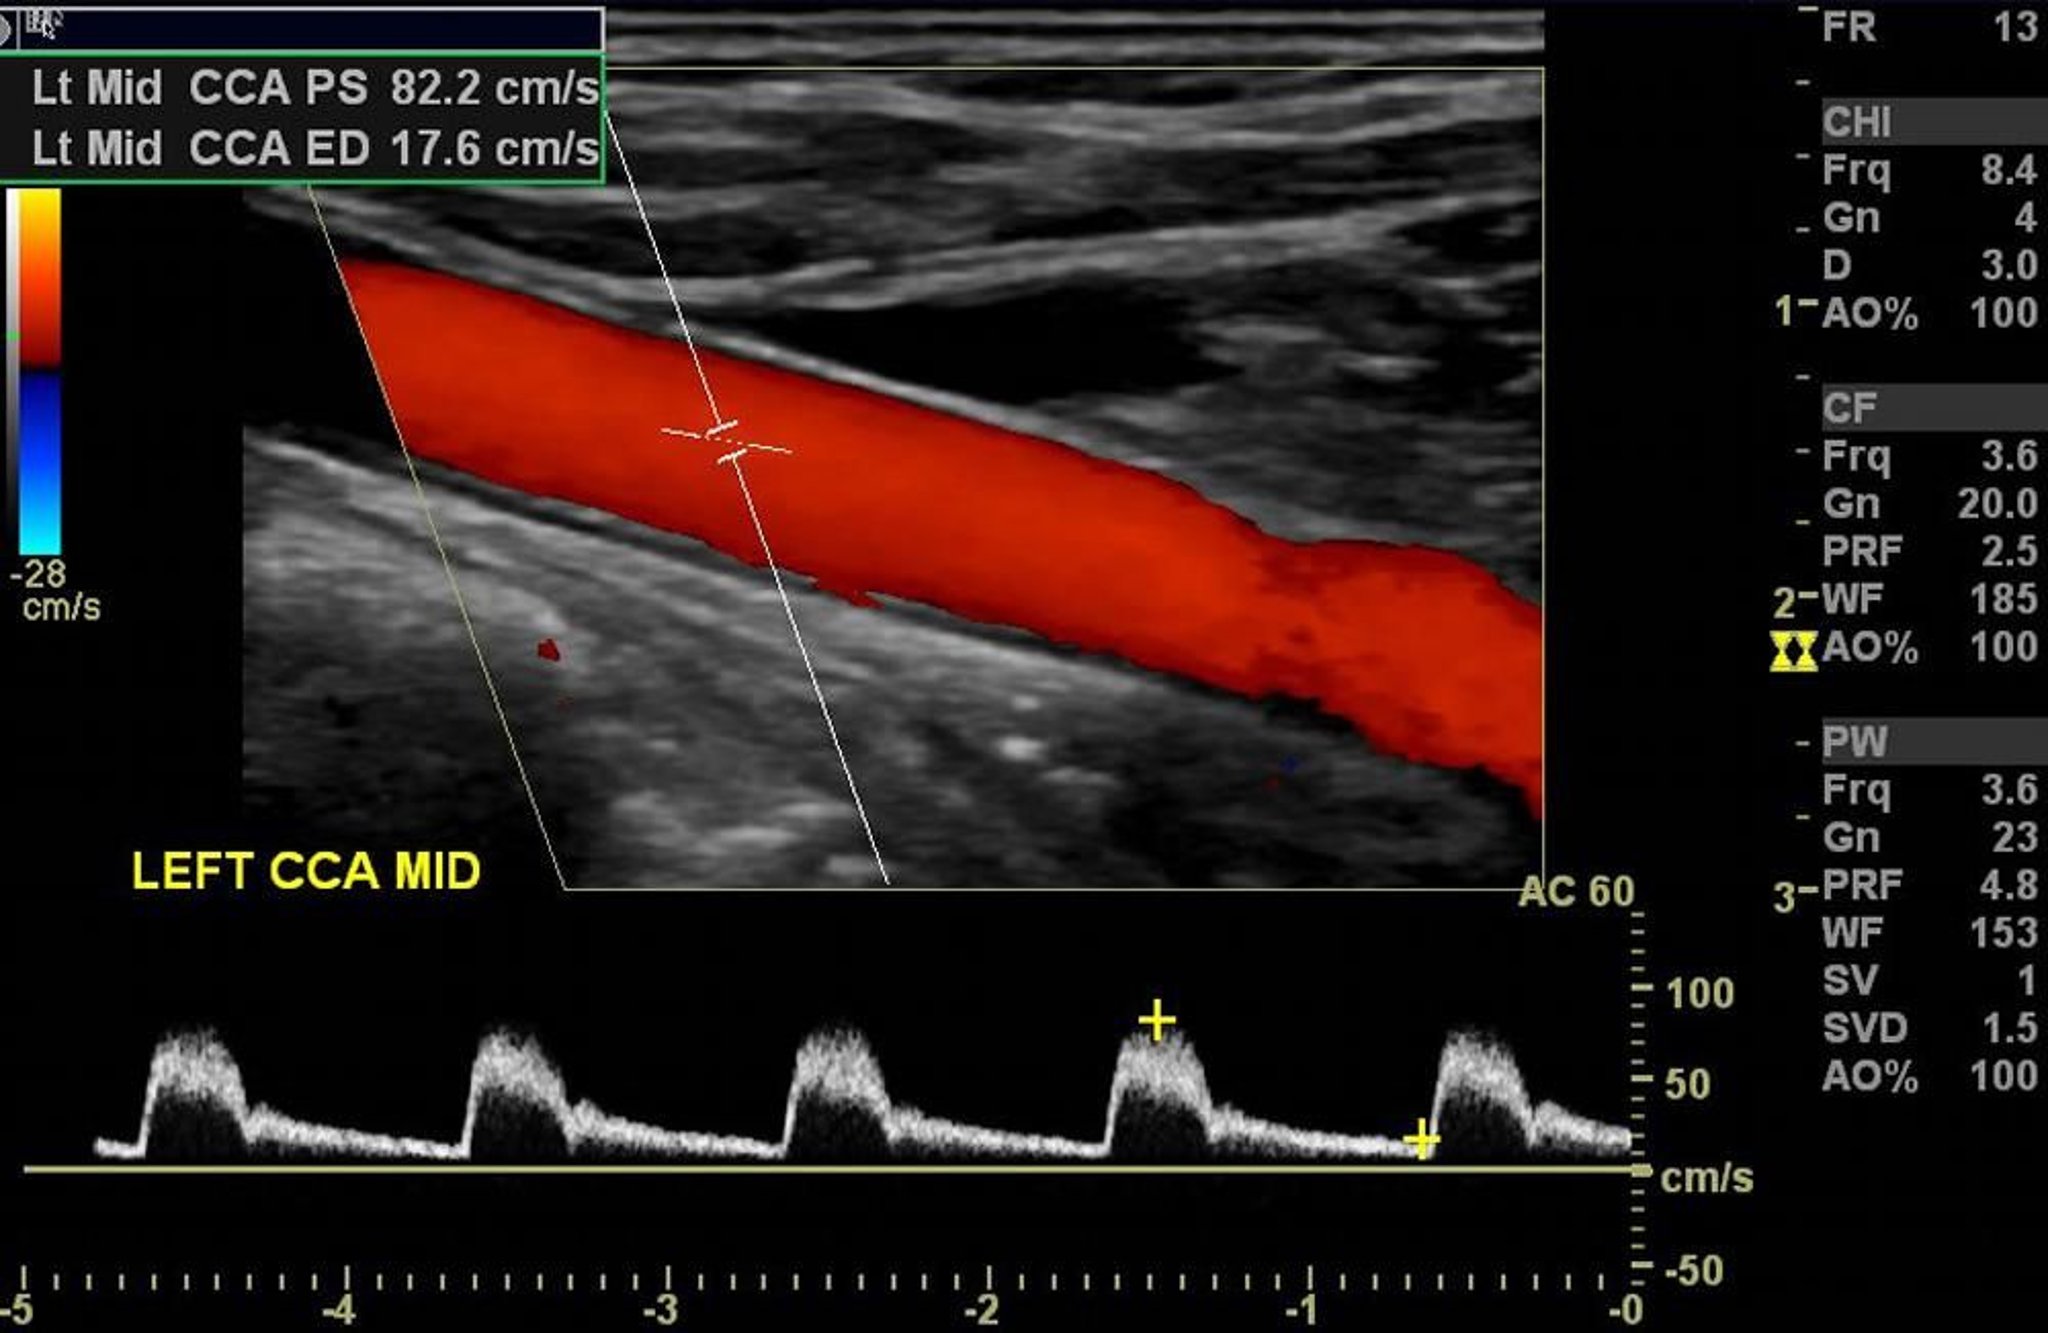

La ecografía Doppler color de la arteria carótida izquierda muestra flujo normal arterial sin estenosis significativa.

Image courtesy of Hakan Ilaslan, MD.